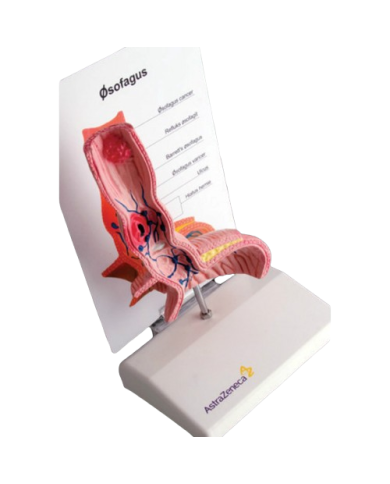

Modello anatomico PER FORNITURE CASE FARMACEUTICHE

Modello anatomico PER FORNITURE CASE FARMACEUTICHE

Modello anatomico PER FORNITURE CASE FARMACEUTICHE

Modello anatomico PER FORNITURE CASE FARMACEUTICHE

Modello anatomico PER FORNITURE CASE FARMACEUTICHE

Modello anatomico PER FORNITURE CASE FARMACEUTICHE

Modello anatomico PER FORNITURE CASE FARMACEUTICHE

Modello anatomico PER FORNITURE CASE FARMACEUTICHE

Modello anatomico PER FORNITURE CASE FARMACEUTICHE

Modello anatomico PER FORNITURE CASE FARMACEUTICHE

Modello anatomico PER FORNITURE CASE FARMACEUTICHE

Modello anatomico PER FORNITURE CASE FARMACEUTICHE

Modello anatomico PER FORNITURE CASE FARMACEUTICHE

Modello anatomico PER FORNITURE CASE FARMACEUTICHE

Modello anatomico PER FORNITURE CASE FARMACEUTICHE

Modello anatomico PER FORNITURE CASE FARMACEUTICHE

Modello anatomico PER FORNITURE CASE FARMACEUTICHE

Modello anatomico PER FORNITURE CASE FARMACEUTICHE

Modello anatomico PER FORNITURE CASE FARMACEUTICHE

Modello anatomico PER FORNITURE CASE FARMACEUTICHE

Modello anatomico PER FORNITURE CASE FARMACEUTICHE

Modello anatomico PER FORNITURE CASE FARMACEUTICHE